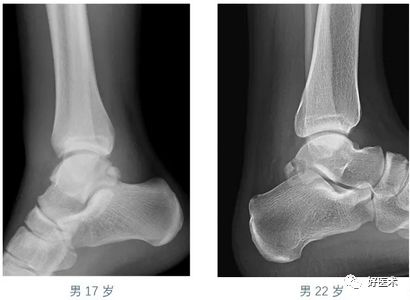

常见的几种骨骼发育异常,容易误诊为骨折,这要特注意!